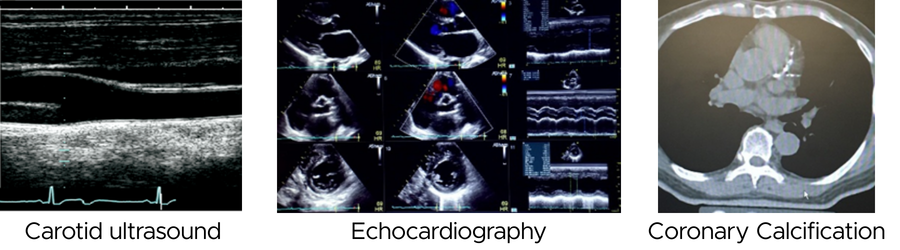

The Tobago Heart Study adds to the wealth of subclinical cardiovascular disease measures that were already added to this longitudinal cohort through Dr. Kuipers’ past work, including carotid ultrasound imaging, pulse-wave velocity assessment, ankle-brachial index measurement, and evaluation of coronary and aortic calcification.